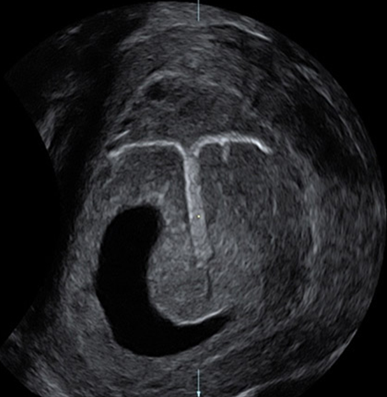

产科_子宫自由解剖切面:宫角妊娠